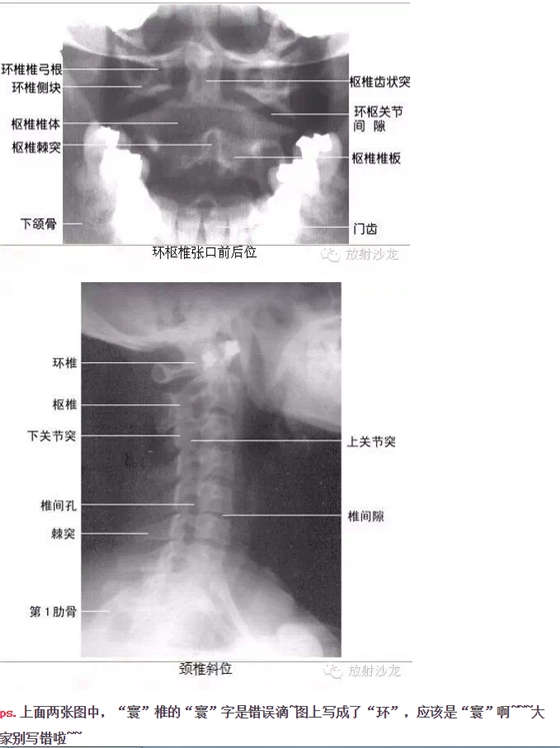

干貨!超級全的X線解剖圖